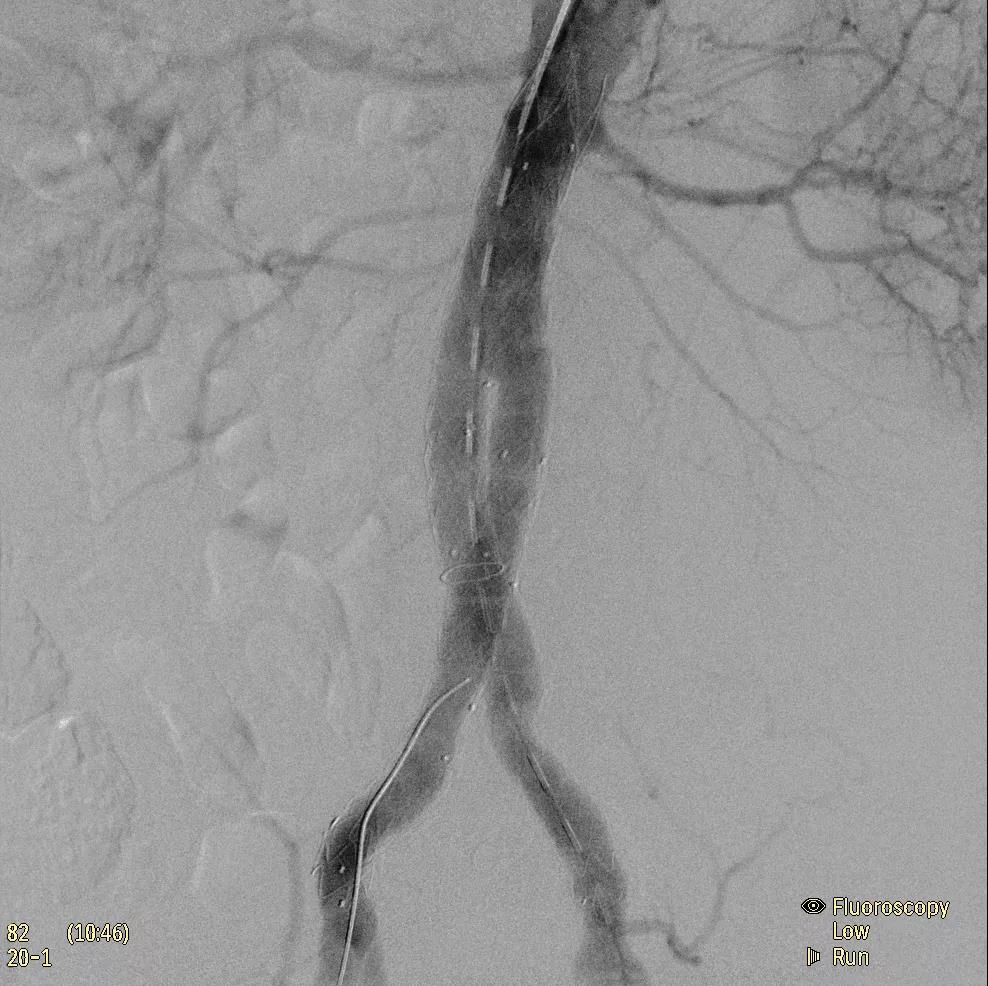

飛利浦于2019年2月18日宣布推出帶扁平探測(cè)器的移動(dòng)式C臂Zenition 70。Zenition 70使用飛利浦第四代Flat Detector系統(tǒng),具有卓越的成像清晰度和靈活性,可執(zhí)行各種情況。

據(jù)器械之家了解到,移動(dòng)式C型臂是X射線系統(tǒng),可帶入手術(shù)室(OR),在整形外科、創(chuàng)傷和血管手術(shù)等各種手術(shù)過程中提供實(shí)時(shí)圖像引導(dǎo)。Zenition70使醫(yī)院能夠最大限度地提高OR性能,增強(qiáng)臨床能力并為員工提供高質(zhì)量的用戶體驗(yàn)。

( Zenition 70匯集了圖像捕獲,圖像處理,易用性和多功能性方面的創(chuàng)新。)

在快速增長(zhǎng)的圖像引導(dǎo)微創(chuàng)手術(shù)領(lǐng)域 ,手術(shù)干預(yù)的范圍和復(fù)雜性在繼續(xù)增加,需要治療的患者數(shù)量也在增加。為了以更低的成本治療更多的患者,醫(yī)院需要具有不同能力的多功能C臂組,以便容易地適應(yīng)不同類型的手術(shù)和不同操作者的需要。Zenition 70易于在手術(shù)室之間移動(dòng),易于在患者周圍定位并且操作直觀。

飛利浦Zenition 70支持整個(gè)醫(yī)療保健機(jī)構(gòu)提高OR性能。平臺(tái)類似平板電腦的用戶界面和簡(jiǎn)單的統(tǒng)一工作流程意味著一旦操作員學(xué)會(huì)在平臺(tái)上使用一個(gè)系統(tǒng),他們就可以輕松地操作它們。該系統(tǒng)可在任何介入或外科手術(shù)過程中快速直觀地拍攝傻瓜相機(jī)。Zenition的緊湊設(shè)計(jì),位置記憶功能(僅適用于Zenition 70)和BodySmart軟件,即使在圖像增強(qiáng)器或平板探測(cè)器的邊緣也能捕捉快速一致的圖像,將C臂重新定位的需求減少45%。

( Zenition 70采用與Azurion平臺(tái)相同的圖像處理算法。

為了獲得清晰的高質(zhì)量圖像,Zenition 70 采用了與公司Azurion平臺(tái)相同的圖像處理算法,可提供患者解剖結(jié)構(gòu)的高清可視化和更大的可視區(qū)域。飛利浦的MetalSmart軟件等功能可確保圖像質(zhì)量,該軟件可自動(dòng)調(diào)整圖像的對(duì)比度和亮度,以便在視野中存在金屬物體(如植入物)時(shí)提高圖像質(zhì)量 - 這一特性使Zenition 70在整形外科中特別有用。